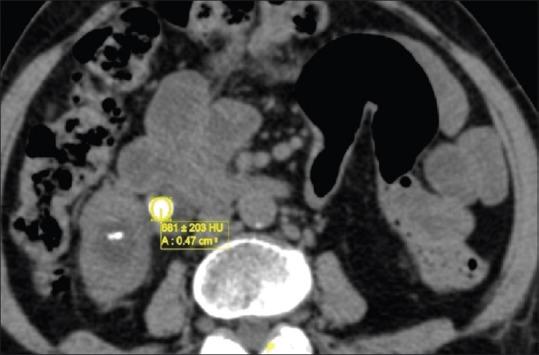

The purpose is to study the association of stone, ureteral, and renal morphometric parameters with the relevant outcome variables, i.e., complication rate, stone-free rate (SFR), and operating time of ureterorenoscopic lithotripsy. Although a safe procedure, it still occasionally has major complications. Computed tomography (CT) scan is often performed to diagnose ureteral calculi, providing opportunities for ureteral morphometry that may have a bearing on the outcome of the procedure.

MATERIALS AND METHODS

Ureteric, renal, and stone morphometric parameters were measured from CT of the abdomen and pelvis of the 110 patients with ureteral calculi who underwent ureteroscopic lithotripsy (URSL). Data were collected retrospectively in 25 patients and prospectively in 85 patients. Association of these parameters with the outcome variables of the procedure mentioned above was studied.

RESULTS

On univariate analysis, body mass index, stone size, and maximum ureteral wall thickness (MUWT) were found to have a significant association with URSL complications, SFR, and duration of surgery. On multivariable analysis, only MUWT was found to be an independent risk factor for URSL complications. In 90% of total patients with residual stones, MUWT was found to be >4.8 mm.

CONCLUSION

Ureteral wall thickness of >4.8 mm is associated with prolonged duration of surgery and lower SFR. Patients with ureteral wall thickness of >4.8 mm at the site of ureteral stone who are planned for URSL must be counseled about the higher chances of residual stones and the need for additional procedure.